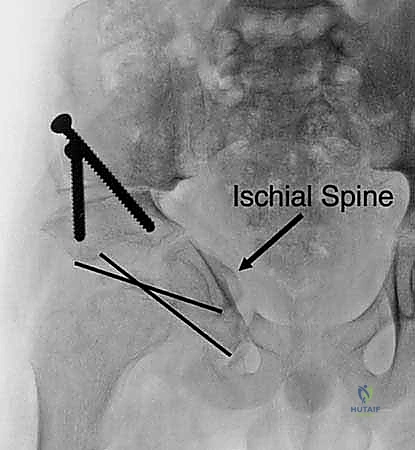

3. مرحلة القطع العظمي (The Three Osteotomies)

هنا تكمن عبقرية الإجراء. يتم استخدام مناشير جراحية دقيقة لعمل قطوع في:

* عظم الإسك (Ischium): العظم السفلي الخلفي للحوض.

* عظم العانة (Pubis): العظم الأمامي للحوض.

* عظم الحرقفة (Ilium): العظم العلوي العريض للحوض.

بمجرد اكتمال هذه القطوع الثلاثة، يصبح التجويف الحقي (الكوب) منفصلاً تماماً عن بقية الحوض، مع بقاء إمداداته الدموية سليمة.

4. إعادة التوجيه والتدوير (Rotation & Redirection)

باستخدام أدوات خاصة، يقوم الدكتور هطيف بتدوير التجويف الحقي الحر في ثلاثة أبعاد (للأمام، وللخارج، وللأسفل) حتى يغطي رأس عظم الفخذ بشكل مثالي وميكانيكي سليم. يتم التحقق من الزاوية الجديدة فوراً داخل غرفة العمليات باستخدام جهاز الأشعة السينية المتحرك (C-arm).